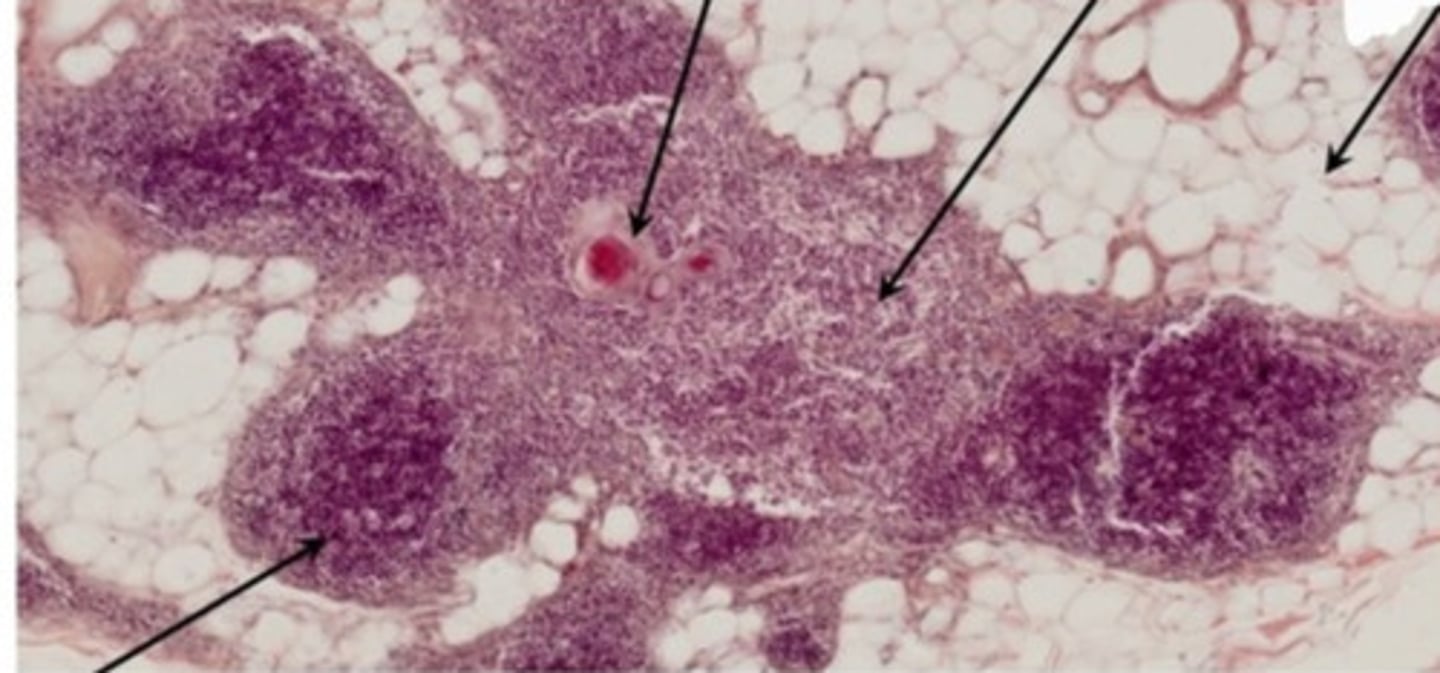

Grasica młodociana (H+E)

Grasica inwolucyjna (H+E)

Węzeł chłonny (H+E)

Śledziona (H+E)